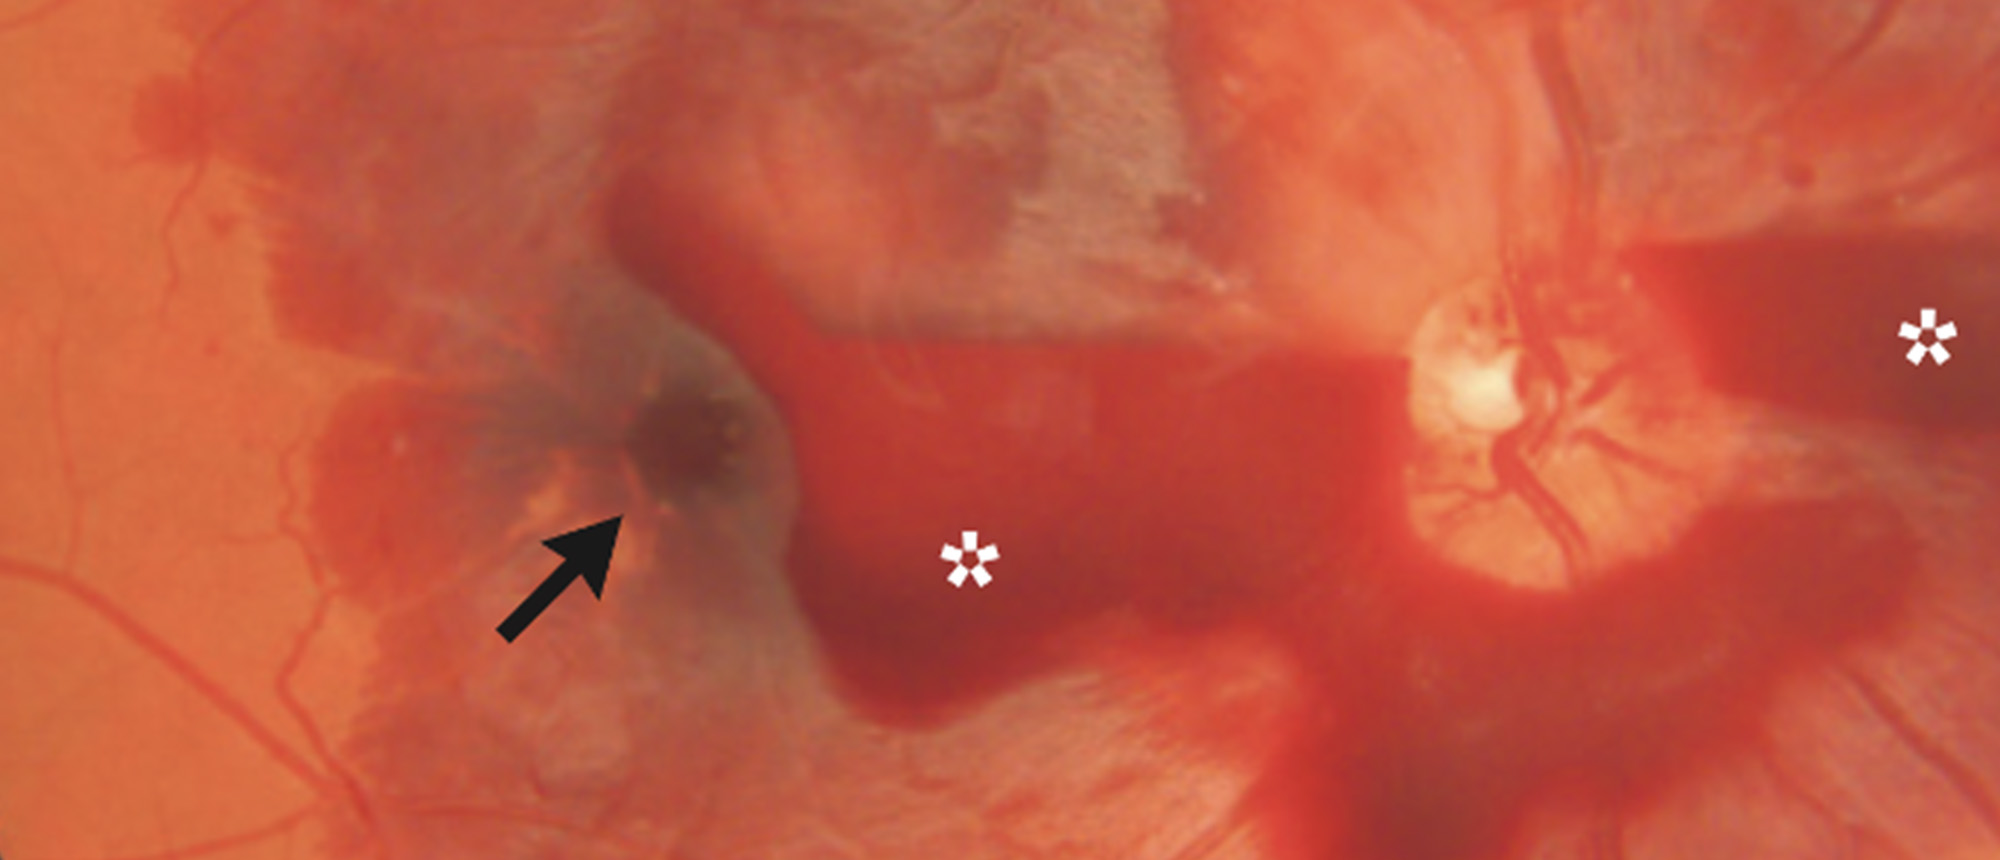

Choroidal Metastasis A patient presented to the Bascom Palmer Eye Institute with blurred vision in the left eye for 5 days. Past medical and ocular history was unremarkable. Past social history was notable for 25 pack-year smoking history. Visual acuity in the right eye was 20/20. Visual acuity in …